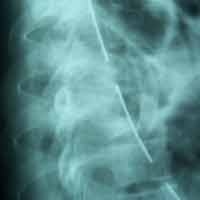

Post-op AP view